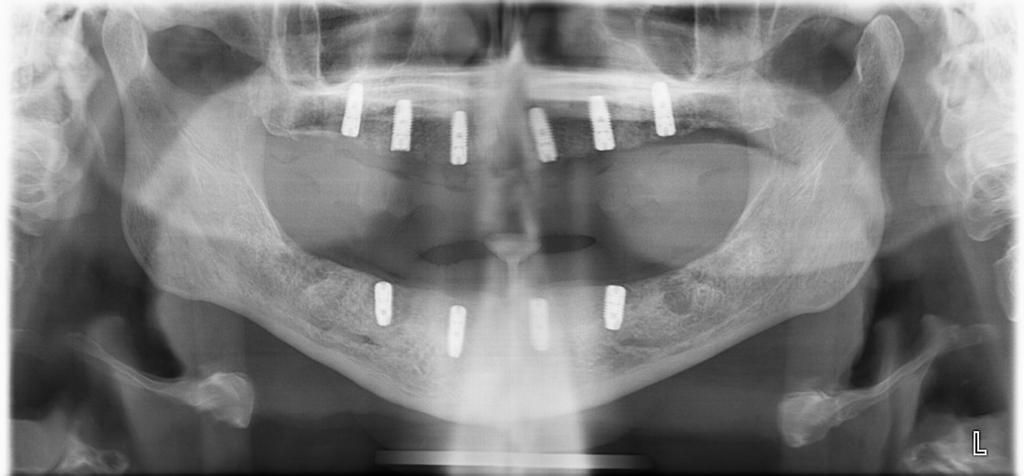

Il paziente nella foto, come si può vedere seguendo la linea del tempo è passato da una situazione di mancanza di denti all’inserimento degli impianti e alla protesizzazione del mascellare superiore in un’ora e 15 minuti. Ciò può essere fatto combinando le tecniche della chirurgia guidata e del carico immediato, qualora le condizioni siano idonee.

il paziente ha inserito gli impianti e ha messo i denti dopo solo 1 ora e 15 minuti